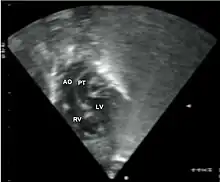

Abbreviations: LV and RV=left and right ventricle, PT=pulmonary trunk, VSD=ventricular septal defect, PS=pulmonary stenosis.